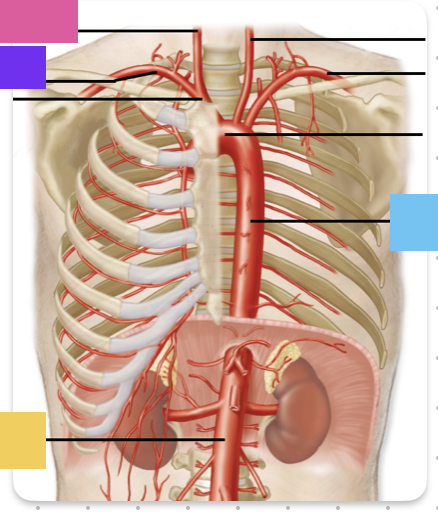

ascending aorta

aortic arch

brachiocephalic trunk (blue)

right common carotid artery

right subclavian artery

left common carotid artery (grey)

left subclavian artery (black)

descending aorta

thoracic aorta

abdominal aorta